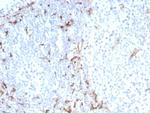

CD163 (Monocyte and Macrophage Marker) Antibody in Immunohistochemistry (Paraffin) (IHC (P))

CD163 (Monocyte and Macrophage Marker) Antibody (9332-RBM14-P1) in IHC (P)

Formalin-fixed, paraffin-embedded human tonsil stained with CD163 Recombinant Rabbit Monoclonal Antibody (M130/8822R). HIER: Tris/EDTA, pH9.0, 45 min. 2°C: HRP-polymer, 30 min. DAB, 5 min. {{ $ctrl.currentElement.advancedVerification.fullName }} 验证信息 View more